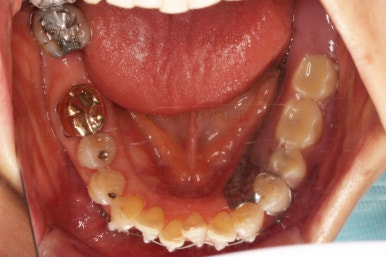

우선 장치를 부착하고요.

가지런하게 하면서 치간삭제 및 기존 떼워진 수복물을 제거한 뒤에 틈을 만들거나 모아줘요.

잇몸에서 주욱 빠져나와서 길어보이던 치아를 다시 잇몸 속으로 원위치 시키는 작업을 같이 해줘요.

점점 부산부분교정을 통해 가지런해지면서 틈새가 모이는 걸 볼 수 있어요.

치아가 없는 부분은 틀니도 병행해서 사용하셨고요.

잇몸이 워낙 약하시다보니 힘을 가하는 방향대로 움직이기도 했지만 과반응이 나타나기도 하고 원치 않는 부분에 새로 틈새가 생기기도 했어요.